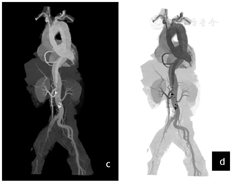

冠脉CTA图像:夹层累及右冠状动脉起始部,起始部管腔中度狭窄,狭窄程度约65%(图3a~c).

Ⅰ型主动脉夹层,夹层范围上自主动脉根部下至右侧髂内外动脉、左侧髂总动脉起始部,夹层累及右冠状动脉、头臂干、左颈总动脉、左锁骨下动脉、腹腔干及左肾动脉;右侧髂总动脉及髂内外动脉大范围受累显影差并血栓形成;左肾显影差。